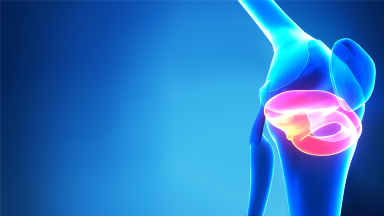

Fachexpertin für Endoprothetik an Knie- und Hüftgelenken - ClarCert

Spezielle Orthopädische Chirurgie mit operativer Tätigkeit